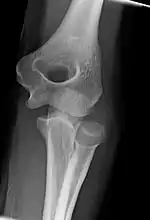

Left: Lateral X ray of a dislocated right elbow

Right: AP X ray of a dislocated right elbow

Dislocation

X-ray of ventral dislocation of the radial head. There is calcification of annular ligament, which can be seen as early as 2 weeks after injury.[29]

Elbow dislocations constitute 10% to 25% of all injuries to the elbow. The elbow is one of the most commonly dislocated joints in the body, with an average annual incidence of acute dislocation of 6 per 100,000 persons.[30] Among injuries to the upper extremity, dislocation of the elbow is second only to a dislocated shoulder. A full dislocation of the elbow will require expert medical attention to re-align, and recovery can take approximately 8–14 weeks.